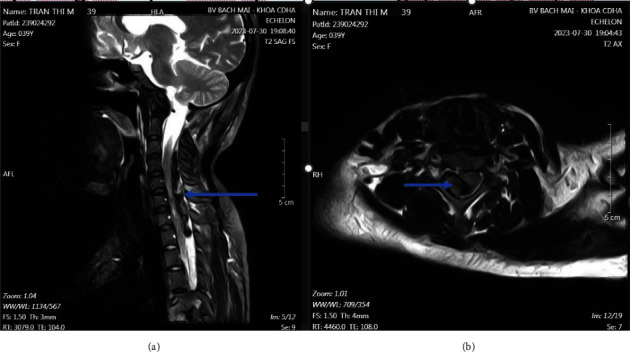

Spinal epidural hematoma (SEDH) is a rare but serious complication associated with spinal anesthesia (SA). We present an unusual case of cervical SEDH occurring 24 h after a lumbar puncture for a cesarean section. The patient, who was on low-dose aspirin due to preeclampsia, initially exhibited neurological symptoms resembling a stroke. Despite a normal magnetic resonance imaging (MRI) of the brain, further investigations revealed a SEDH located between the C3 and T1 segments, well beyond the L3-L4 puncture site. Although coagulation tests were normal, this case underscores the potential risk of low-dose aspirin in affecting platelet function, which may contribute to SEDH development. It also emphasizes the importance of considering spinal MRI when neurological symptoms arise after SA, even if initial cranial MRI results are normal. She underwent emergency C3-T1 laminectomy through a dorsal midline approach. Her motor, sensory, and sphincter functions fully recovered at follow-up.